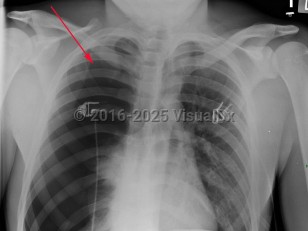

Tension pneumothorax

PneumomediastinumPneumomediastinum